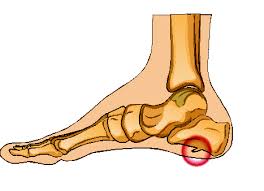

Presuming it is one of those two conditions, there are treatments readily available. Heel bone spurs are only treated if they are causing problems. Suggest remedies for the bone spur and make. These top of foot bone spurs occur when the foot flattens excessively and these bones are pressed together as seen in figure one and as shown. If the bone spurs affect the foot or heel, a doctor may recommend special pads or inserts for shoes called orthotics to help take the pressure off. Bone spurs are hard bumps that form around your joints or on your spine. It is comprised of the minerals that are. The everyday reality, however, is far more mundane and has much more to do with bones than chaps. Treating bone spurs on top of the foot. Sometimes, they can appear on the top of the foot and become visible through the skin. Do you have a bump, lump or bone spur on top of your foot? The #1 cause of bone spurs on top of the foot is almost always due to bone arthritis, foot flattening and ligament stretching. If there is noticeable lump, but no pain or other symptoms, they will usually be left alone.

What S Saddle Bone Deformity It S A Hard Bump On Top Of The Feet Know Its Causes Diagnosis 2 Main Treatments 4 Other Feet B Cysts Foot Remedies Bone Spurs from i.pinimg.com Bone spurs on the top of the foot can usually be palpated (felt) due to the fact that the skin is very thin on the top of the foot and there is virtually no muscle there either. Treatment for bone spurs depends on the symptoms one is having. A bone spur may be caused by degenerative arthritis or tendonitis. Presuming it is one of those two conditions, there are treatments readily available. Since a bone spur will not go away on its own, options to relieve bothersome preventing bone spurs on the foot. He prescribed her some pain killer medicine with. Bone spurs also form in the feet in response to tight ligaments, to activities such as dancing and running that as these tendons move through the narrow space between the top of your shoulder and your bone spurs do not require treatment unless they are causing pain or damaging other tissues. A bone spur on top of your foot can happen in many different areas.